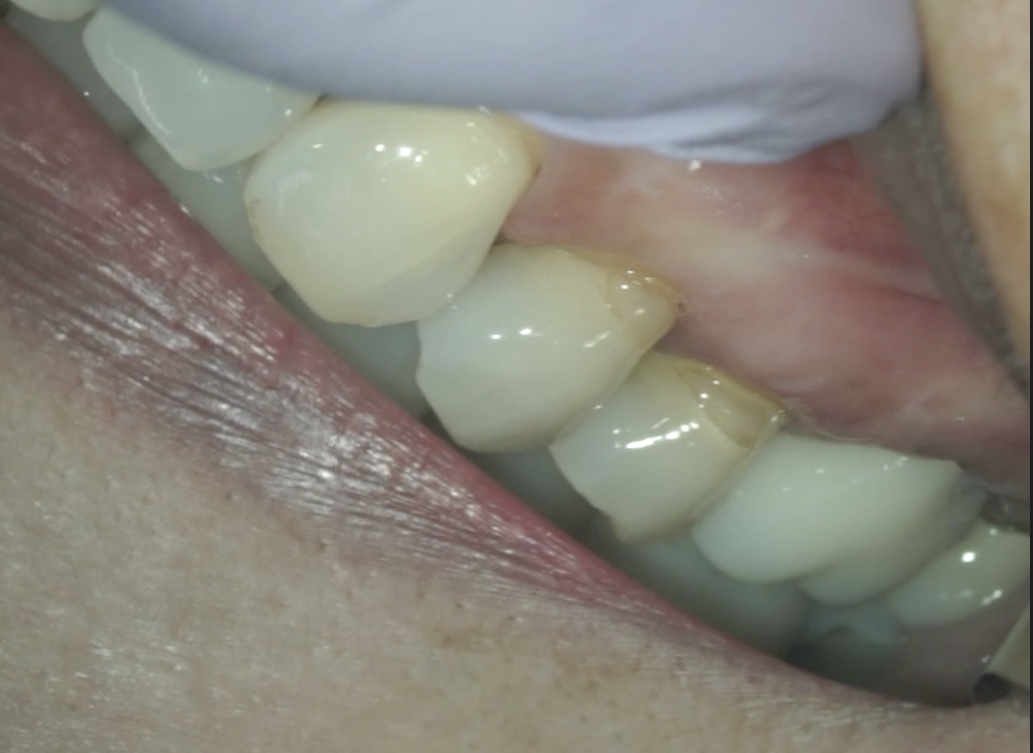

Sinus tract, 臨床症状は消失した。

術後の瘢痕も目立たない。